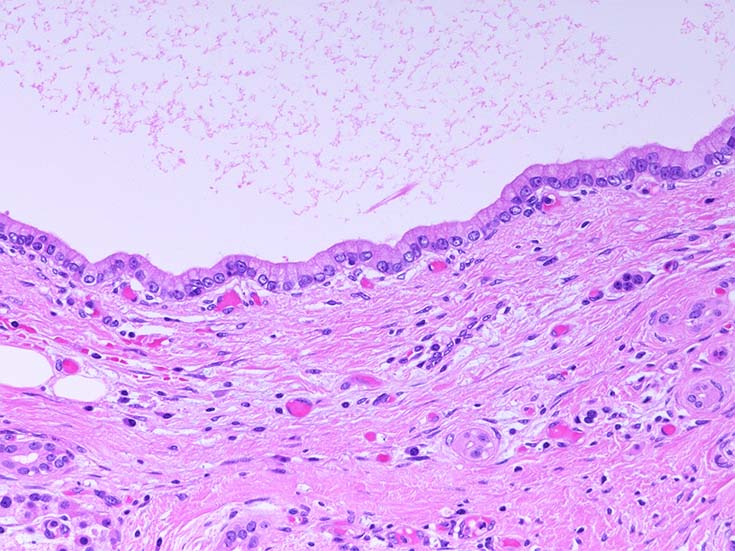

膵上皮内腫瘍性病変 pancreatic intraductal neoplasm(PanIN)*16

Low-grade PanINとhigh-grade PanINの分類

low-grade PanIN

PanINの図譜はJohns Hopkins The Sol Goldman Pancreatic Cancer Research CenterのHome page*19から引用.

1. PanIN-1; PanIN発生の初期段階. 組織学的に, 核異型を伴わない, 核の極性が保たれている.

• telomereの短縮

• KRAS変異

• p16/CDKN2A変異

• Mucin(MUC)発現